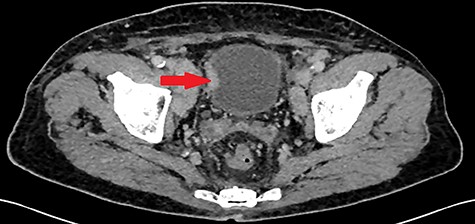

A 55-year-old, nonsmoking patient with no medical or surgical history who had a pulmonary adenocarcinoma diagnosed 1 month prior was referred to the urology department for macroscopic hematuria. Actually, the patient had initially presented with hemoptysis and a computed tomography (CT) scan revealed a right lower lobar pulmonary nodule, which biopsies concluded to a moderately differentiated adenocarcinoma. Interrogation revealed urinary frequency, urgency and several episodes of intermittent hematuria for 3 months. Physical examination showed a patient with an impaired general condition, without other abnormalities and a normal urine color. The urine dipstick revealed a hematuria at two crosses. The biological workup showed no abnormalities and the prostate specific antigen (PSA) level was at 2 ng/ml. The thoracic-abdominal-pelvic CT scan, performed for his lung cancer, showed, in addition to the lung mass of the right lower lobe with a right mediastinal adenopathy, a thickening of the bladder wall enhancing on the right lateral wall, an upper urinary tract free of any lesion and no distant metastases (Fig. 1). Cystoscopy under locoregional anesthesia was performed, showing a normal endoscopic appearance of the urethra and prostate gland, with inflammatory and bullous lesions on the bladder trigone and right lateral wall, which were biopsied using a resector (Fig. 2).

Thickening of the right lateral wall of the bladder enhancing at arterial time on CT scan (arrow).